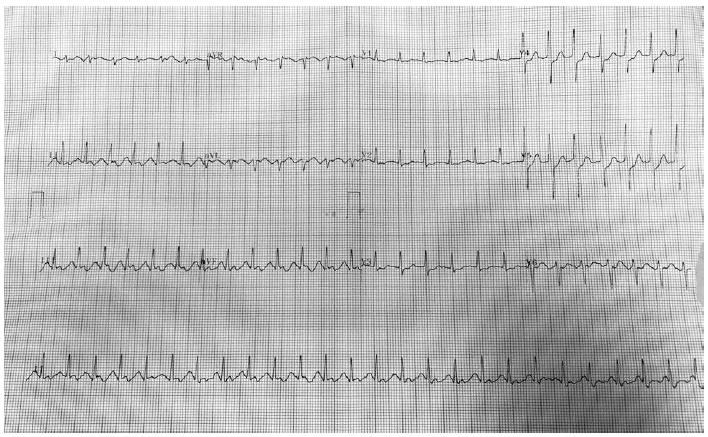

Paciente do sexo masculino, 60 anos, hipertenso, admitido para cirurgia de osteossíntese de fratura de rádio distal esquerdo. Foi realizado bloqueio de plexo braquial com 20 mL de lidocaína a 2% com vasoconstrictor, sob ansiólise. Durante a injeção do anestésico, o paciente relata sensação de “batedeira no peito”, mas sem outros sinais ou sintomas. O monitor mostra FC de 150 bpm, PA de 160 x 90, SpO2 95%. Você interrompe a injeção e solicita a enfermagem um eletrocardiograma de 12 derivações, que foi realizado e está ilustrado pela figura:

Diante do quadro apresentado, assinale a opção que exibe o diagnóstico CORRETO: